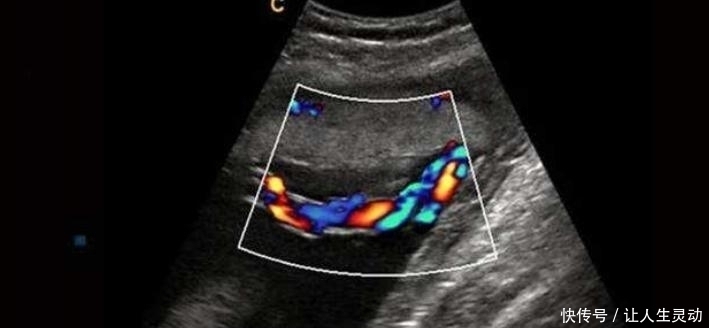

通过B超也能发现胎儿脐带扭转异常,从B超影像上能清晰地看见

文章插图